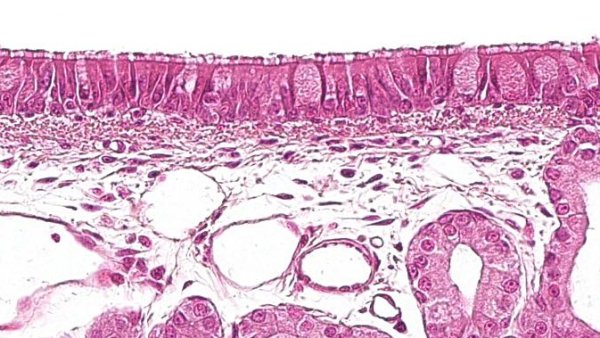

¿Qué tipo de células forman el sistema de defensa respiratorio en los cerdos? ¿Cómo se organizan y se comunican entre sí?

¿Qué tipo de células forman el sistema de defensa respiratorio en los cerdos? ¿Cómo se organizan y se comunican entre sí?

Este artículo analiza las distintas lesiones micro y macroscópicas causadas por los virus de PRRS, PCV2, el virus de la gripe porcina y el coronavirus respiratorio porcino.

Este artículo describe las principales lesiones que caracterizan las principales neumonías bacterianas. Aunque la mayoría son agentes oportunistas, hay dos agentes bacterianos primarios que son capaces de causar lesiones por sí mismos.

M. hyopneumoniae participa en la mayoría de las coinfecciones en casos del complejo respiratorio porcino. ¿Cómo actúa y qué efectos tiene?